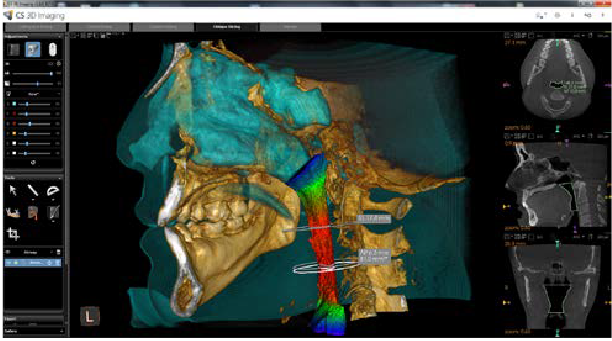

Análisis de vías respiratorias

Analizar las vías respiratorias superiores con mediciones automáticas y vistas de colores 3D para visualizar fácilmente las restricciones y los cambios en las vías respiratorias.